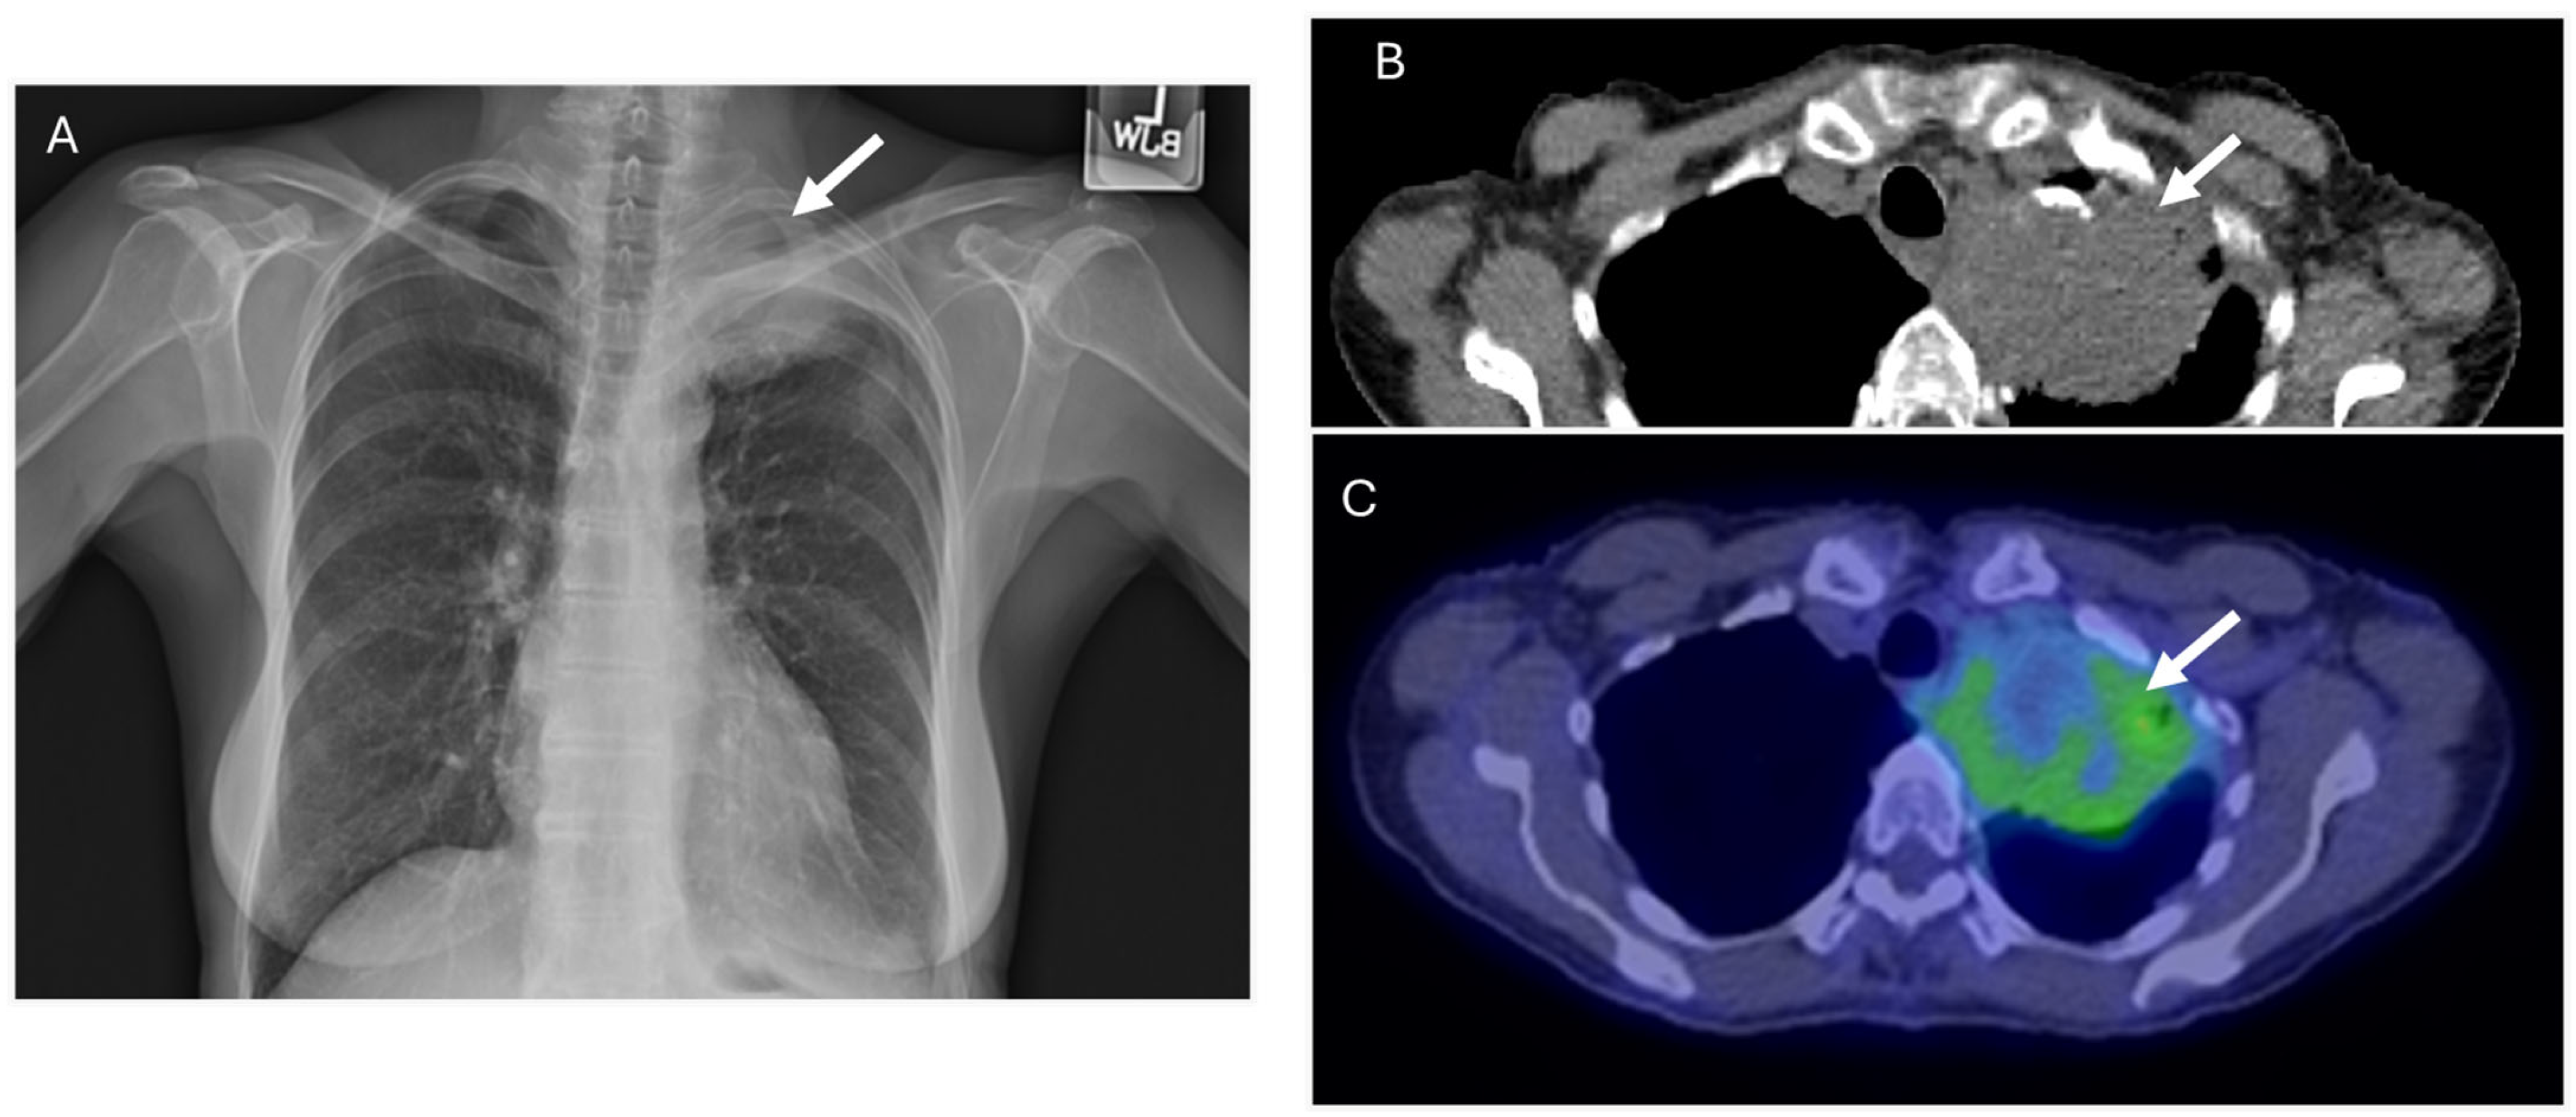

5.3. Schnitzler Syndrome